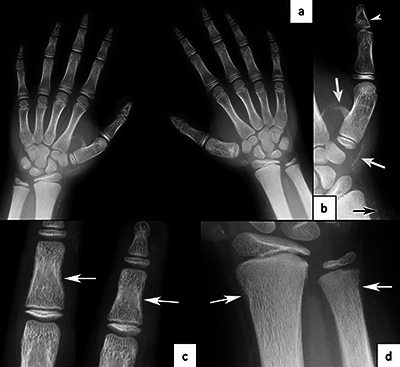

Teaching point: Some genetic syndromes have characteristic features that allow for their diagnosis to be made based on radiological findings.